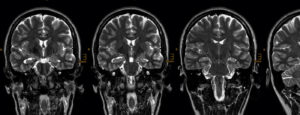

MRI, englisch für Magnetic Resonance Imaging. Feststellen der Liäsonen / Verletzungen an meinen Nervenbahnen mittels Bildern.

EEG, die Elektroenzephalografie. Die Aufzeichnung der elektrischen Aktivität des Gehirns.